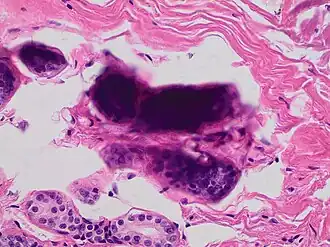

A crush artifact is an artificial elongation and distortion seen in histopathology and cytopathology studies, presumably because of iatrogenic compression of tissues. Distortion can be caused by the slightest compression of tissue and can provide difficulties in diagnosis.[2][3] It may cause chromatin to be squeezed out of nuclei.[4] Inflammatory and tumor cells are most susceptible to crush artifacts.[4]